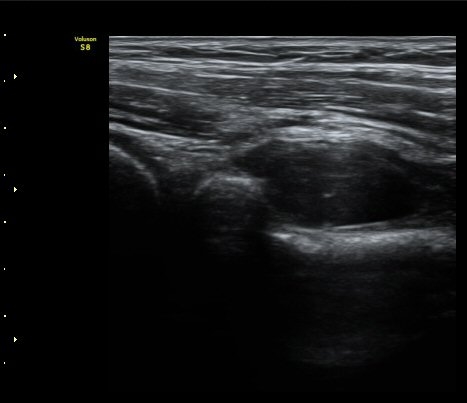

ŽÃËÀÚ¸¦ ¿ä°ñµÎ ºÎÀ§·Î À̵¿ÇÏ´Ï ¿ä°ñµÎ Ç¥Ãþ¿¡ Àú¿¡ÄÚ ³¶Á¾ÀÌ °üÂûµÇ°í ³¶Á¾ÀÇ ¿ÜÃø¿¡¼­

Èİñ°£½Å°æÀÌ ¾Ð¹ÚµÇ°í ÀÖ´Ù(±×¸² 2).